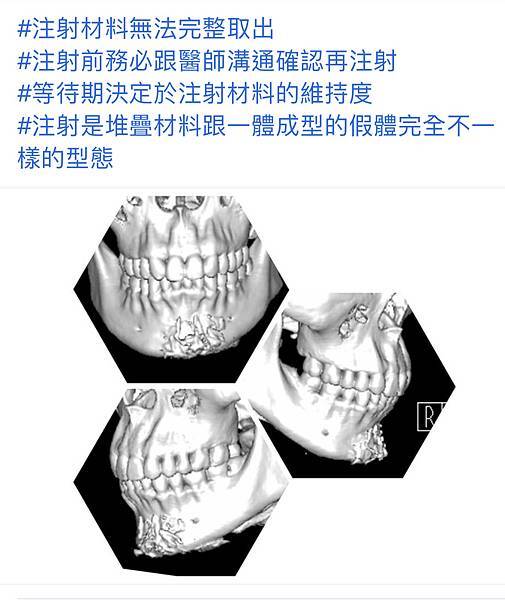

雖然注射下巴填充接受度高,但問題不少也難以移除:吸收偏斜、組織變硬,外型難掌握。因此注射都必須保守,適不適合要醫師判斷!

上 圖注射填下巴